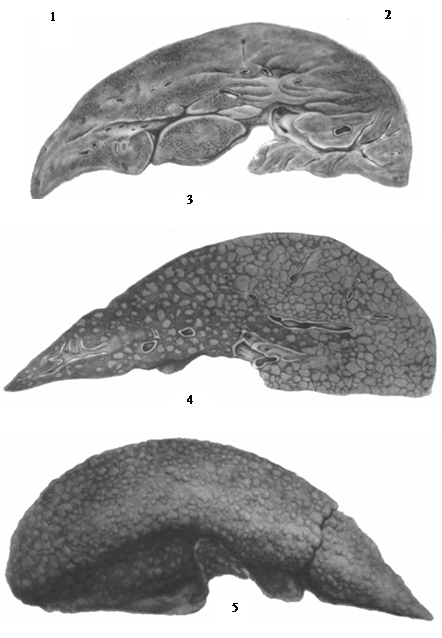

Морфологическим своеобразием отличается Б. б. у новорожденных, возникающая в результате трансплацентарной передачи вируса плоду от беременной больной или вирусоносительницы. Своеобразие это заключается в присутствии многоядерных гигантских клеток типа симпластов, встречающихся при вирусном гепатите также у детей раннего возраста (рис. 3), иногда и у взрослых. Есть основания предполагать (Тер-Григорьева), что внутрипеченочные атрезии желчных путей, обнаруживаемые у новорожденных, могут быть патогенетически связаны или с внутриутробным гепатитом плода, или с порочным развитием печени плода в результате трансплацентарного воздействия вирусной инфекции беременной. Описываются также врожденные

В небольшом проценте случаев обычное течение Б. б. осложняется массивным некрозом печеночных клеток, что сопровождается клинической картиной острой недостаточности печени и квалифицируется анатомически как острая токсическая дистрофия печени или острая атрофия. Отмечаемые макроскопически дряблость печени и уменьшение ее размеров (рис. см. отд. табл., рис. 3) зависят но только от гибели паренхимы, но и от уменьшения кровенаполнения в спавшейся строме. При более медленном развитии некрозов — при подострой дистрофии печени — на фоне большой убыли паренхимы и воспалительных инфильтратов четко выступают процессы регенерации и некоторая коллагенизация стромы, что обусловливает более плотную консистенцию печени. Исход острой и подострой дистрофии печени — летальный или в узловую гиперплазию с рубцеванием, или в постнекротический цирроз печени.

2. Хронический прогрессирующий гепатит с рецидивами и обострениями характеризуется сочетанным диффузным поражением паренхимы и стромы печени и соответствует клинико-анатомическому понятию цирроза печени (см. рис. 4 и отд. табл., рис. 4 и 5). Имеющиеся при этом воспалительные инфильтраты в строме, дистрофически некротические изменения печеночного эпителия, процессы узловой регенерации, диффузное разрастание соединительной ткани с нарушением сосудистой структуры, с образованием портально-печеночных анастомозов ведут к полной перестройке печени, вовлекая в страдание ряд органов и систем организма. В связи с этим возникают различные клинические варианты течения: с выраженным гепатолиенальным синдромом Банти и явлениями гиперспленизма и анемии, с гепато-церебральным синдромом, изредка с картиной гепатолентикулярной дегенерации. Бурный рост регенератов в печени может привести к развитию первичного рака печени с метастазами в другие.